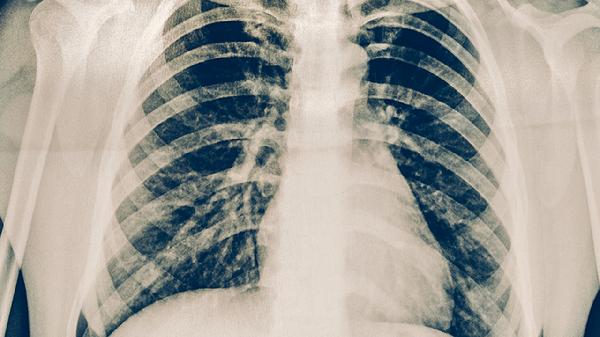

胸部X线能发现肺部结核病灶,典型表现为上肺野斑片状阴影、空洞形成等。该检查对活动性肺结核诊断价值较高,但早期病变可能漏诊,且存在辐射暴露风险。胸部X线异常需进一步做痰检确认。